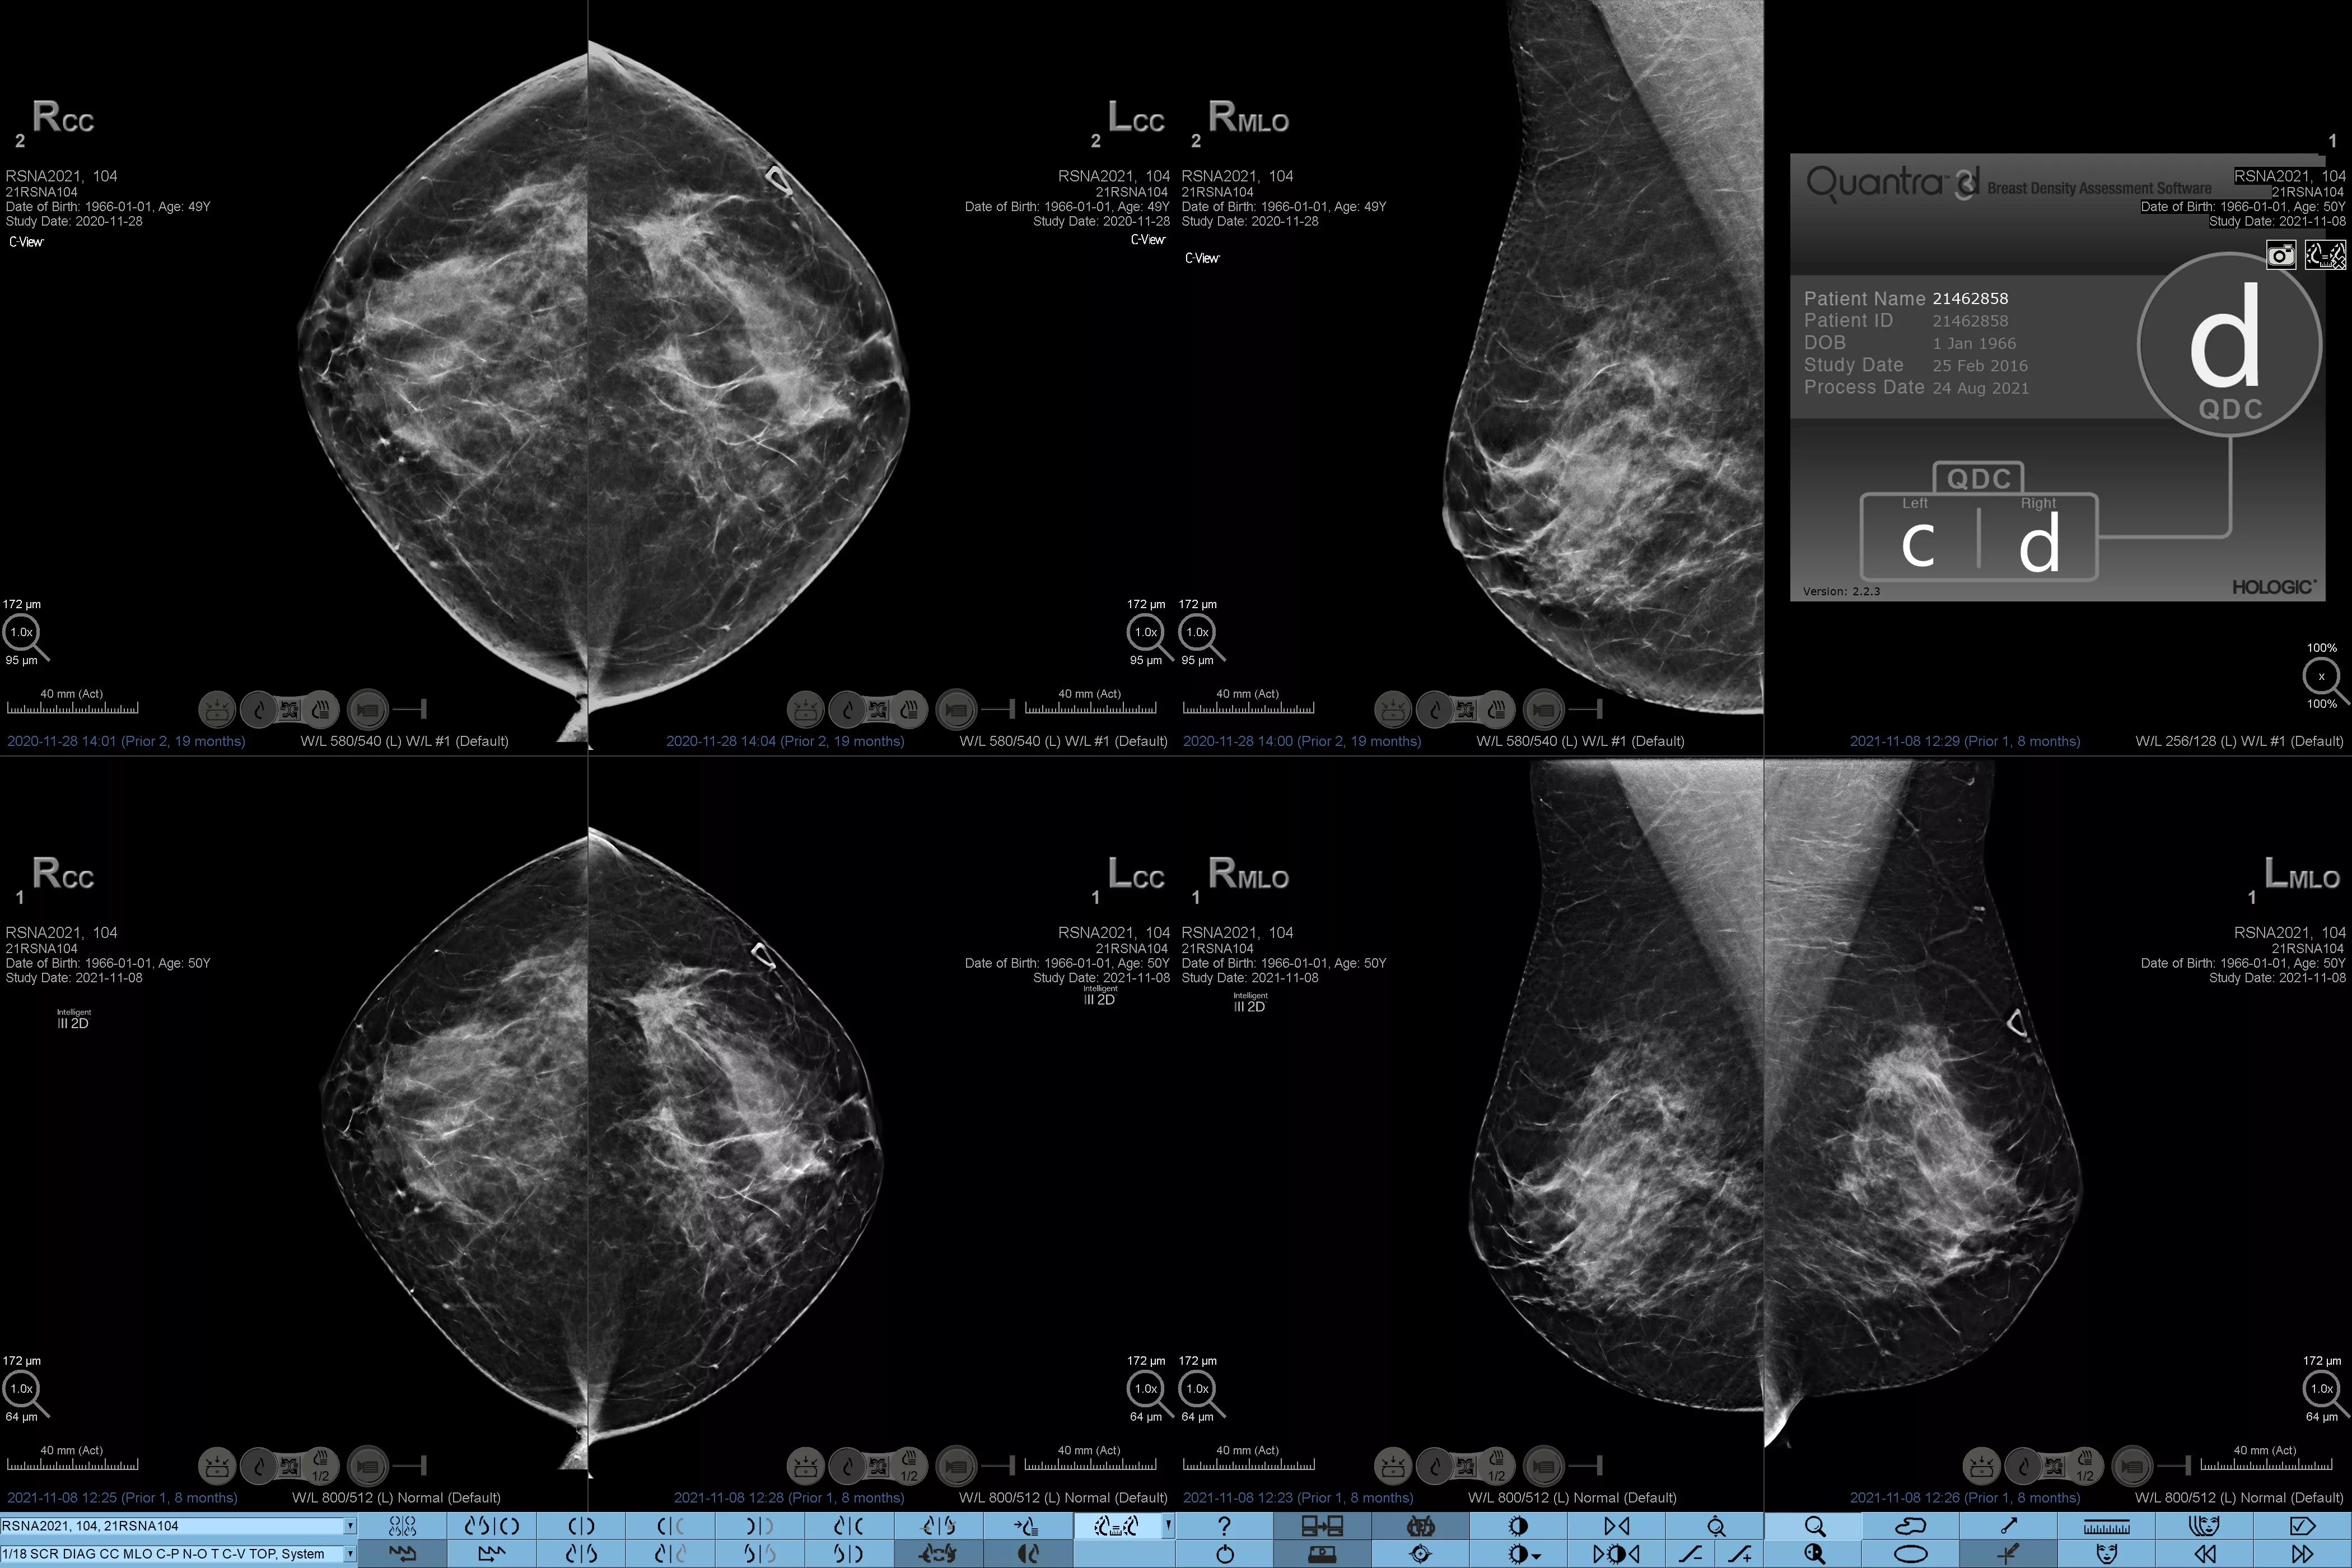

Het is bekend dat een hogere borstdichtheid het risico van een vrouw op borstkanker vergroot.1 De behoefte aan nauwkeurige, objectieve analyses is daarom cruciaal. Aangedreven door machine learning analyseert Quantra-technologiesoftware zowel 2D™- als tomosynthesebeelden op verdeling en textuur van parenchymweefsel. Het deelt borsten in vier categorieën voor borstsamenstelling in, in overeenstemming met de richtlijnen van de American College of Radiology (ACR) BI-RADS Atlas 5e editie.2

Naast volume spelen het patroon en de textuur van fibroglandulair weefsel mogelijk net zo'n belangrijke rol bij de mammografische voorspelling van kankerrisico.3-5 Door de textuur en het patroon van de borst te analyseren en te categoriseren, kan onze technologie de nauwkeurige informatie leveren die u nodig hebt om consistentere en betrouwbaardere scorebepaling te verkrijgen en zelfverzekerd patiëntspecifieke screening te ontwerpen.

Objectief machine-learningalgoritme dat de borstdichtheidscategorie toewijst op basis van analyse van de textuur en patronen van het borstweefsel.

Risicocategorieën8